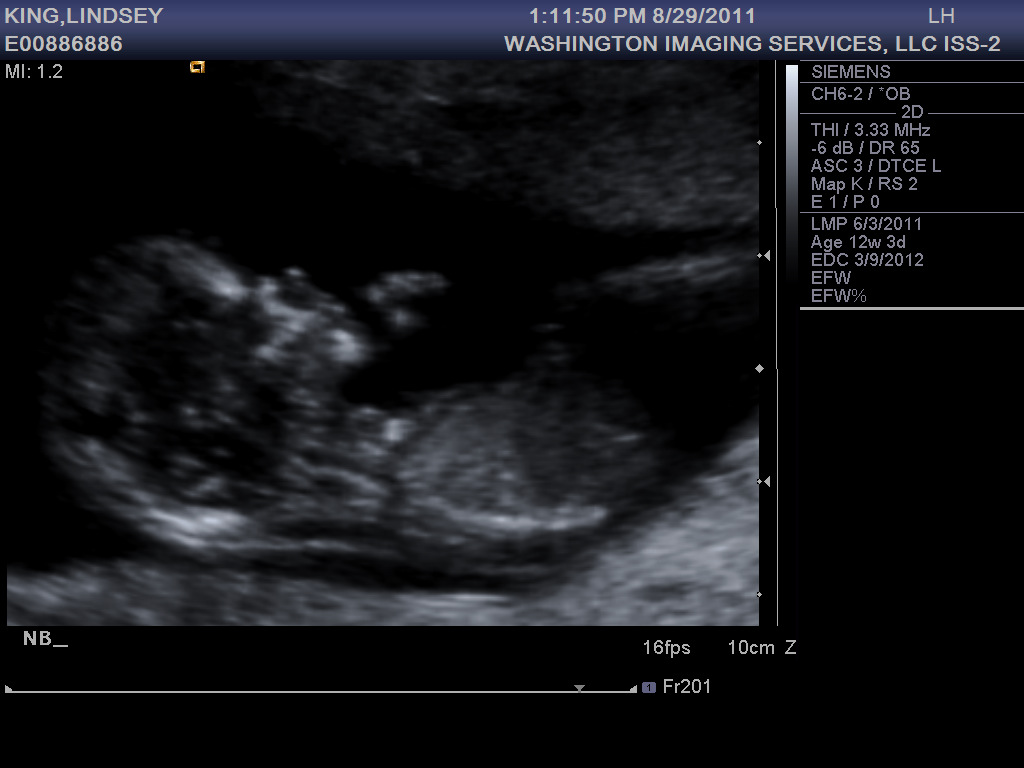

At my ultrasound last week, baby #3 was 13 weeks along and looking healthy and active. He or she was moving around so much the tech had to work extra hard to get measurements. Is this an indication of what to expect later on?

The first trimester is behind me now, thank goodness. So far I’m still exhausted and nauseous, but I expect these symptoms to wane in the coming weeks. Did I mention how T-I-R-E-D I’ve been? By 2pm I just want to crawl into bed in the fetal position, but there are still hours left until Jonathan’s home, then there’s dinner, putting the boys to bed, and by the time we finally hit the hay, I can’t fall asleep! So I toss and turn like a rotisserie chicken until at last sleep comes. But even then I wake up several times in the night, never really getting that sweet REM sleep… and then it’s time to get up and do it all over again. Okay, I’ll stop complaining now. I had it easy the first two times around, I should be thankful. And really, it could be a lot worse. On the up side, I get to spend my days with the two sweetest little boys in the world!

13 week bump shot